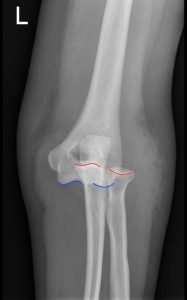

Posterior Elbow Dislocation, AP XRay, dislocated, Annotated. JETem 2016

Posterior Elbow Dislocation